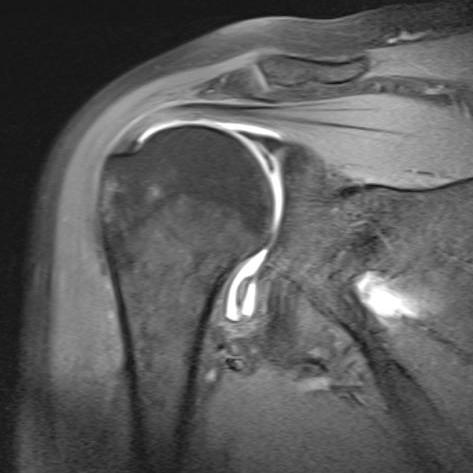

Die MRT ist inzwischen unverzichtbarer Bestandteil der Diagnostik am Bewegungsapparat. Muskeln, Sehnen, Bänder, Knochen und Knorpel, sowie deren Krankheitszustände lassen sich in unvergleichlicher Weise differenzieren. Einige Krankheitsbilder wie z.B. das "traumatische Knochenödem" oder die knöcherne Stressreaktion sind überhaupt erst durch die MRT bekannt geworden.